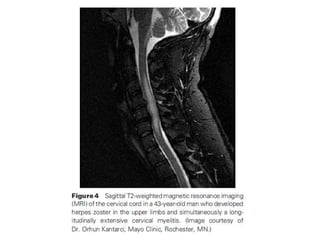

• infection (eg, enteroviruses, West Nile virus,

herpes, central nervous system Lyme disease,

mycoplasma)

• Infections including enteroviruses, West Nile

virus, herpes viruses, HIV, human T-cell leukemia

virus type 1 (HTLV-1), Zika virus , neuroborreliosis

(Lyme), Mycoplasma, and Treponema pallidum .